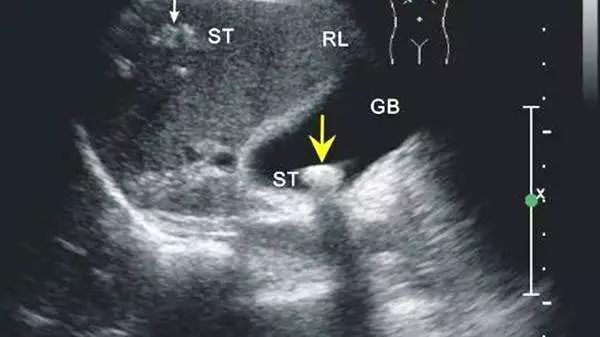

肝癌筛查:千万记住甲胎蛋白+B超

很多人体检时都会选择做腹部B超,以为这样可以查出肝部问题,其实很容易漏诊。

专家建议:高危人群(乙肝病毒和/或丙肝病毒感染、长期酗酒、非酒精脂肪性肝炎、食用被黄曲霉毒素污染食物、各种原因引起的肝硬化、以及有肝癌家族史等),年龄40岁以上,建议考虑每半年筛查一次,国内多数专家建议联合甲胎蛋白检测和肝脏超声检查对肝癌高危人群进行定期筛查,发现异常进一步考虑CT或磁共振检查。